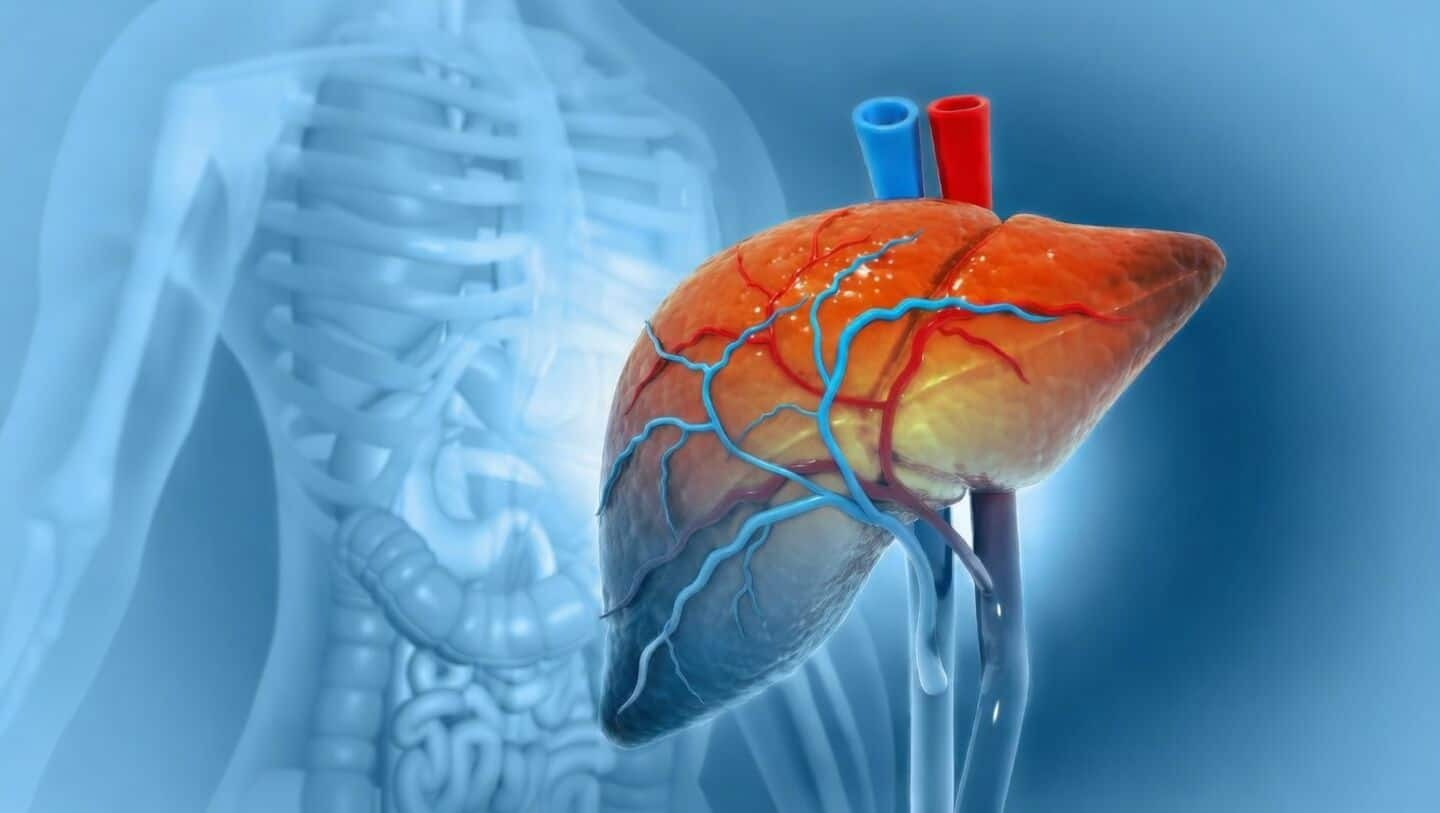

Fatty liver disease (MASLD) is now a major health concern in India, with The Lancet Regional Health - Southeast Asia reporting that more than 38% of the population is affected.

This condition often goes unnoticed but can lead to serious problems like liver damage and even cancer if ignored.